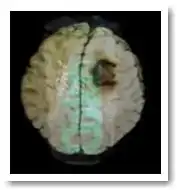

До 1990 года не проводились тесты по влиянию фтора на шишковидную железу. Шишковидная железа или эпифиз – это маленькая железка, расположенная между двумя мезговыми полушариями.

Древние философы, а также Святые Востока считали, что шишковидная железа является местом обитания Души. Эпифиз является центральной точкой взаимодействия между правым и левым полушариями мозга. Это центр всего, что мы осуществляем между духовным и физическим планом. Пробуждение, или активация, этой клетки позволяет вернуться к оптимальному здоровью на всех уровнях.

Шишковидная железа регулирует выделение мелатонина – гормона "молодости", который помогает регулировать достижение половой и духовной зрелости. В свою очередь, мелатонин вырабатывается шишковидной железой из серотонина - вещества, явно связанного с высшей мыслительной функцией человека. Видимо, не случайно просветление сознания требует активизации шишковидной железы; дерево Бо, под которым сидел Будда, было богато серотонином.

Но что не менее важно, так это то, что шишковидная железа отвечает за иммунитет, она при правильной работе защищает тело от вредоносных эффектов, которые свободные радикалы оказывают на мозг.

Одним из инициаторов этого исследования была врач Дженифер Люк из Университета Surrey в Англии. Она доказала, что шишковидная железа первая попадает под удар фтора. Также, согласно исследованию, избыточное количество этого элемента на уровне шишковидной железы приводит к серьезным дисфункциям, провоцируя раннее половое созревание и уменьшая способность организма бороться со свободными радикалами.

Нейтрализацию шишковидной железы чисто теоретически можно провести путем очень сильного воздействия фтора на нее. Фтор может разрушить кости, зубы и эту самую шишковидную железу. Он ее словно бетонирует.

Фтор не выводится быстро из организма, но накапливается в костях и зубах. Недавно также было обнаружено, что он накапливается еще более интенсивно в шишковидной железе, находящейся в середине мозга. Последствия зубного флуорозиса, приносящего серьезный ущерб зубам при ежедневном применении фтор-содержащей пасты уже были задокументированы. Тем не менее, официально продолжается пропаганда использования фтора в целях профилактики кариеса. Тот факт, что фтор может приносить больше вреда, чем пользы, продолжает игнорироваться.

- кальцификация и блокировка шишковидной железы.